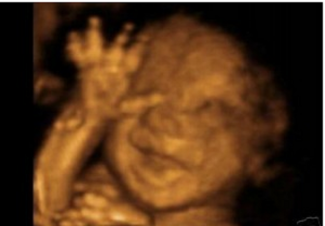

Ak je podľa liberálov bábätko iba zhluk buniek, prečo bránia ženám vidieť ultrazvuk?!